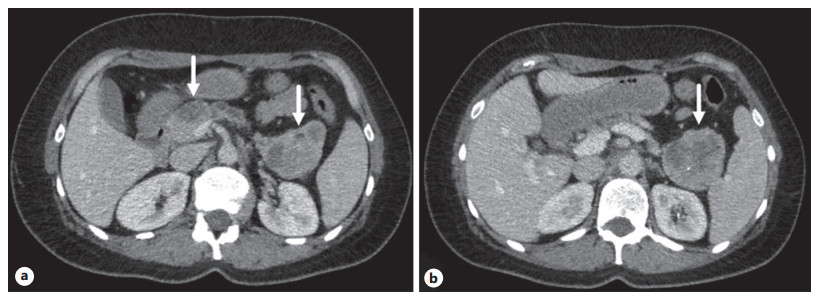

Abstract: Intraductal papillary mucinous neoplasm (IPMN) and solid pseudopapillary neoplasm (SPN) are uncommon cystic tumors of the pancreas. The simultaneous occurrence of these 2 pancreatic neoplasms is extremely rare. We present a case of synchronous solid SPN and IPMN – carcinoma in a 44-year-old female patient. An uncommon surgical treatment was performed – pancreatoduodenectomy with the resection of the pancreas body, resection of the mesentericoportal trunk + distal pancreatectomy, and splenectomy. Part of the pancreatic tissue was preserved.